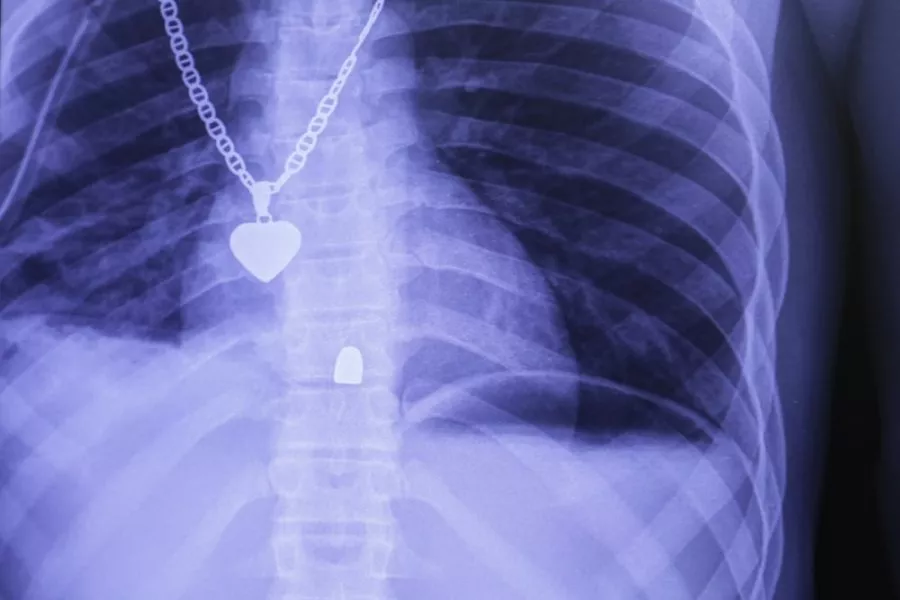

Je to 29letá žena se střelnými ranami. Ruce má oteklé a krvavé. Náš tým lékařů, zdravotních sester a sanitářů se o ni hned začíná starat. Lupiči jí nařídili, aby dala ruce k sobě, pak ji dvakrát postřelili. Rentgen odhaluje dvojitou zlomeninu obou rukou.

Rentgen odhaluje, že nedošlo k poškození plic. Jameson si pár dní u nás v nemocnici pobyde, než se bude moct vrátit domů.

Pacient je při vědomí, ale nemůže hýbat nohama. Nejprve mu zavádíme hrudní katetr, aby se předešlo komplikacím spojeným s krvácením. Potom děláme rentgen a laparotomii — zkoumáme břicho, abychom zjistili, jak moc ho kulka poškodila.

Při operaci se ukázalo, že žádné životně důležité orgány nejsou poškozené. Kulka těsně minula játra. Radiografie potvrdila podezření z pohotovosti: kulka nevyšla z těla a zůstala v pacientově páteři.